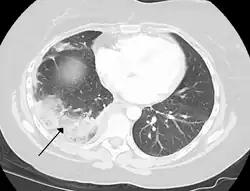

Infarction of the lung due to a pulmonary embolism

By histopathology